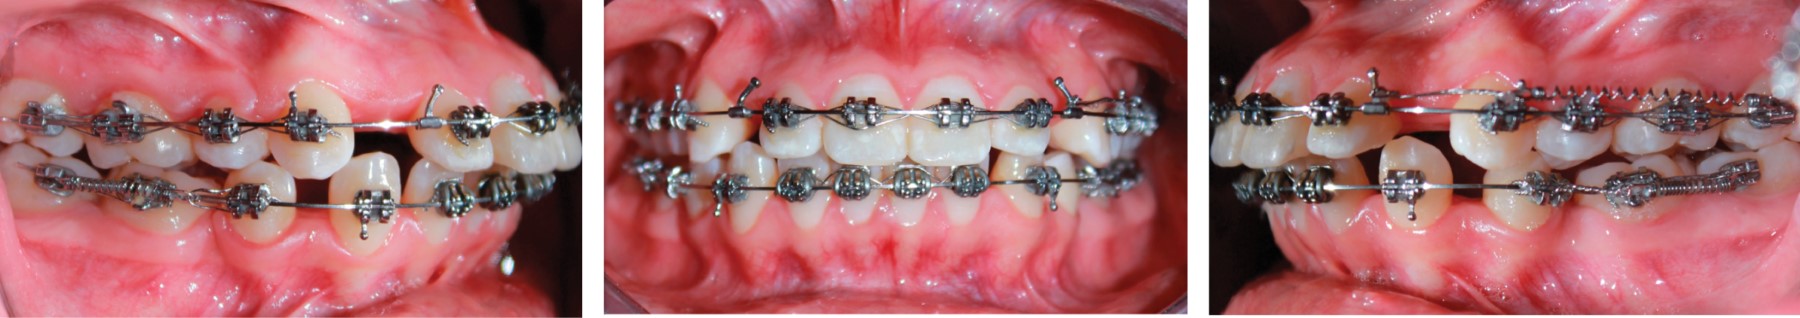

ANCHORAGE RECOVERY

It is becoming more and more frequent in daily practice the patient who was previously treated with premolar extractions and at the time of space closure was complicated and the results were a class II due to the loss of anchorage in addition to other complications that the patient may present, such as being able to offer another treatment to recover the lost relations such as going from a class II to a class I without devices such as pendulums, extraoral arches or mini implants in a considerable time after the patient has already been treated, this is another of the great advantages that the Tip-Edge system offers because thanks to the vertical control and sagittal direction in group of teeth it is possible to recover the relations under the philosophy of the differential movement9 that is to say, firstly tilting the crowns towards distal in group and later the root verticalization recovering class II towards class I with the use of light intermaxillary elastics that with other systems is difficult to obtain due to the action of its bracket increasing the speed of treatment and obtaining functional and esthetic results in record time compared to traditional and preadjusted systems10 (Figure 11).